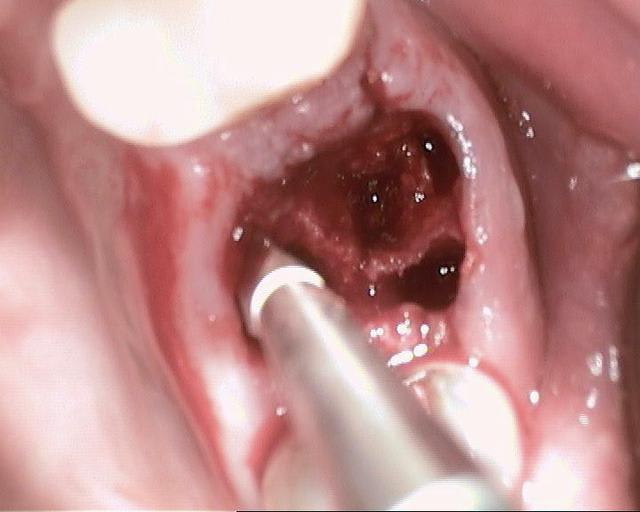

Un patient de 52 ans présente une fracture de racine au site 26.Après division de la racine, extraction de la dent,préparation de la cavité avec un foret conique triangulaire (3 faces,condensation de l´os), puis implantation à 50 Ncm (implant 10mm long, 4,5mm diamètre).Utilisation d´acide hyaluronique pour stimuler la synthèse des ostéoblastes.Pose d´un clip gingival pour préformer la gencive.Après 7 semaines, réalisation d´une empreinte fermée en 5 minutes.Une semaine après, fixation de la couronne définitive ( on observe déjà une ostéointégration).

Pour laisser entrevoir la technique MIMI (Minimale Invasive Method Implantation) développée par le Dr Armin Nedjat voilà la séquence en photos et radios d'un cas d'extraction implantation immédiate technique simplifiée.